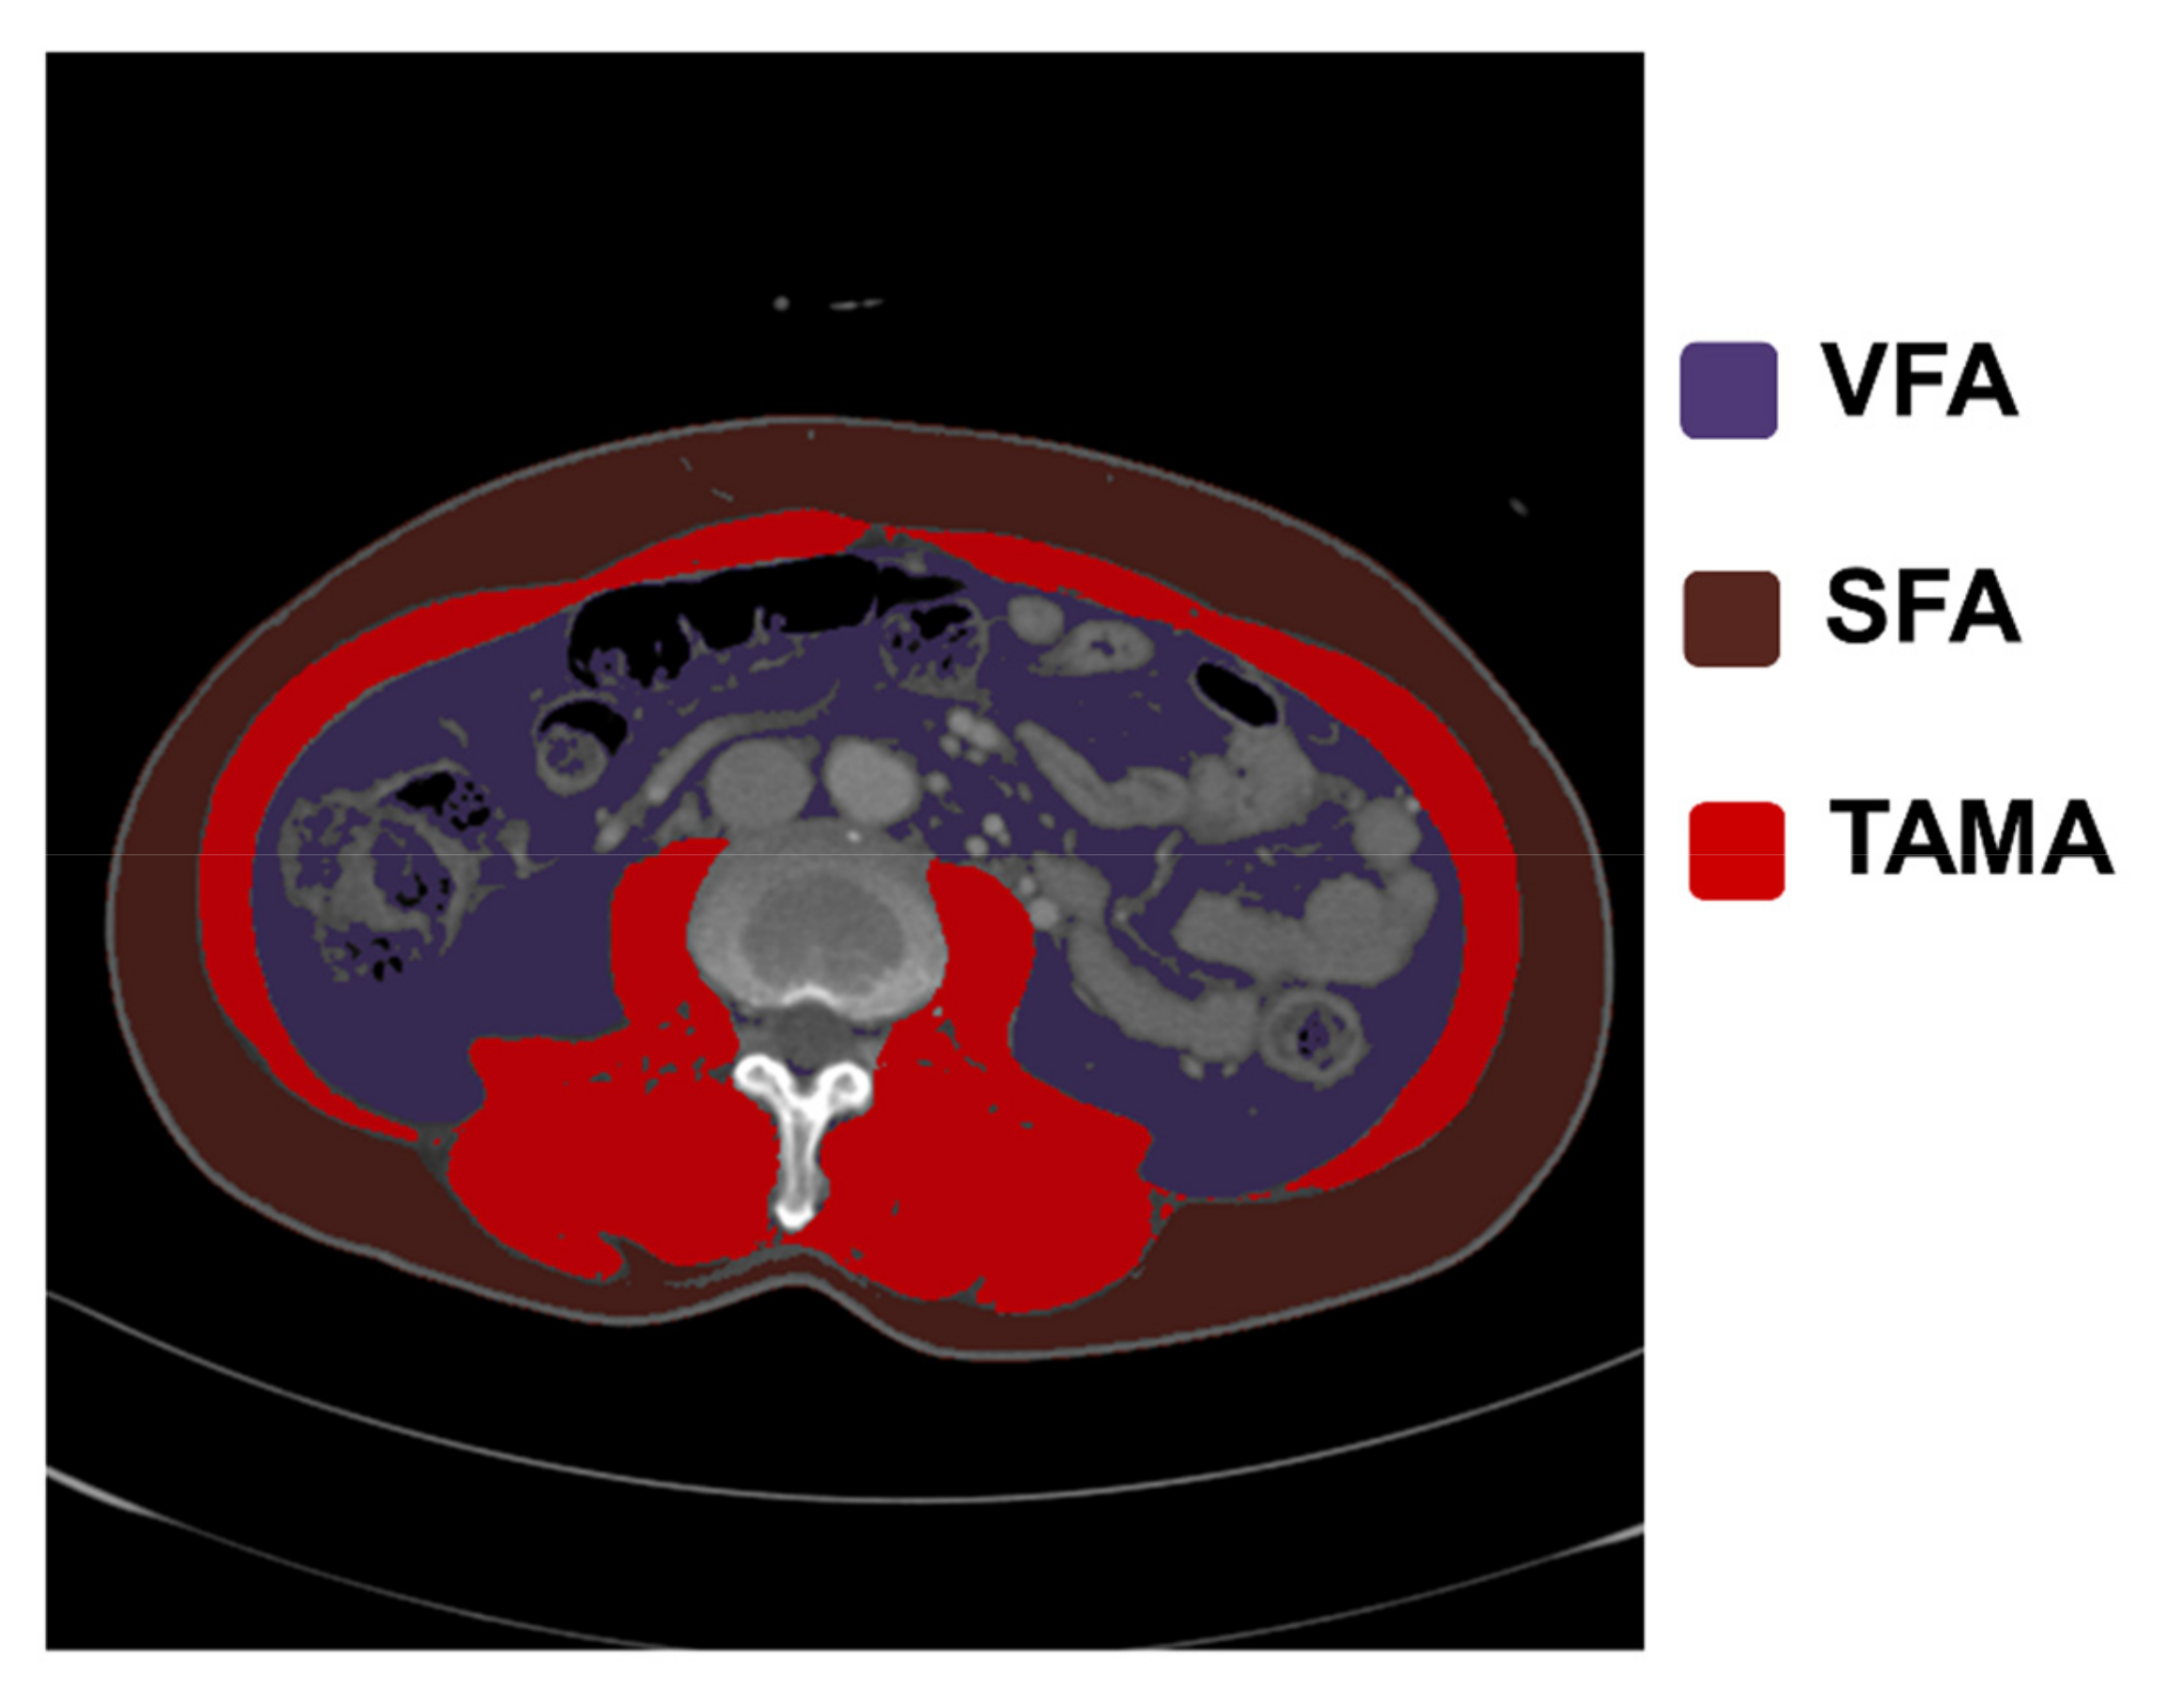

2.4. Analysis of CT Images and Body Composition